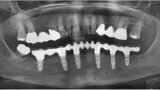

Fig. 1: Panoramic radiograph of the initial dental status.